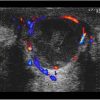

Apxe vú

Apxe vú - Ảnh 2

» Thông tin: Nữ giới – 21 tuổi.

» Lâm sàng: Sưng đau tuyến vú.